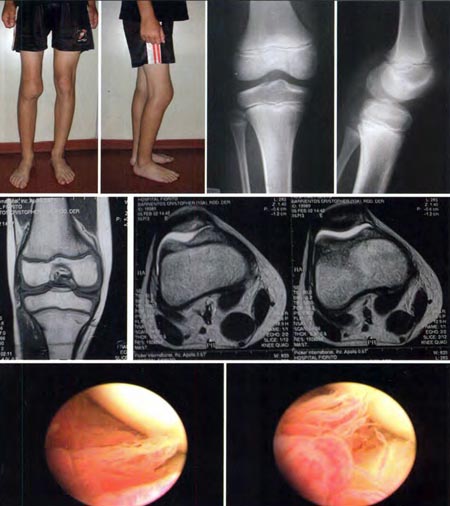

Paciente de sexo masculino de 10 años de edad que consulta por dolor de rodilla izquierda. Al examen físico presenta tumefacción, choque rotuliano (+) y limitación de la movilidad (contractura en flexión de 10°). Se solicitaron radiografías (sin hallazgos patológicos) y RMN donde se observa una masa intraarticular, localizada en el compartimento anterior, recesos lateral y en menor medida el medial. Se realizó biopsia artroscópica de la sinovial que confirmó el diagnóstico de SVNP. El paciente fue intervenido quirúrgicamente por artroscopía a los de 3 meses de la consulta inicial. A los 58 meses de la cirugía permanece asintomático con un rango de movilidad completo (0-135) y sin recidiva clínica. (Fig. 2) En ambos casos se realizó preoperatoriamente resonancia magnética nuclear (RMN) para evaluar la localización y la extensión de la lesión. El diagnóstico fue confirmado previamente con histología. Lue-

go de la inducción anestésica, se coloca al paciente en decúbito dorsal con soporte de rodilla a 90°. Para la resección se utilizaron 4 portales: dos pararotulianos (anterolateral y anteromedial) y dos suprarotulianos (interno y externo), con óptica de 30° para visualizar el compartimento anterior, los recesos lateral y medial. En el postoperatorio se coloca vendaje elástico en el miembro y se indica crioterapia. Se coloca un inmovilizador de rodilla sin descarga de peso durante los primeros tres días para evitar la hemartrosis. Los pacientes son citados a control a la primera y segunda semana del postoperatorio, para evaluar las heridas y el rango de movilidad. A la primera semana se comienza con movilización suave y ejercicios de cadena cerrada de cuádriceps. Luego, en la segunda semana se comienza con fisioterapia. Una vez retornado a la actividad habitual (4-6 semanas aproximadamente), se realizan controles mensuales.

Figura 2: Paciente de sexo masculino de 10 años de edad que consulta por dolor e impotencia funcional de rodilla derecha. A) Aspecto clínico donde se objetiva marcada tumefacción y limitación de la flexo extensión, B) Radiografías sin lesiones objetivables, C) RMN, D) Imagen artroscópica: Vellosidades localizadas en el compartimento medial.